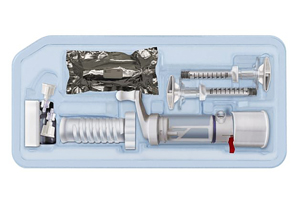

Bacon founded Garwood Medical in Buffalo, New York, in 2014 and licensed the technology behind BioPrax in 2016. The electrical stimulation treatment is thought to help eliminate biofilm infections on knee implants more effectively than antibiotics alone. Two skin-based electrodes adhere like those used during an EKG, while a small needle makes contact with the implant to complete an electrical circuit. The corresponding electrochemical reaction produces hydrogen peroxide and hydroxides to drive up the pH to a bactericidal level that breaks down the biofilm and kills bacteria.

BioPrax is under investigation to be used alongside the DAIR standard of care after the patient is closed, “cleaning up” any remaining bacteria.

BioPrax was accepted into FDA’s Breakthrough Device Program in October 2019. FDA indicated that the technology is a good candidate for the De Novo classification as well, which would lower the Class from three to two. The designation is also welcome news for investors as the company completes its Series C financing.

Garwood Medical has started pre-clinical studies through a grant at the University of Buffalo’s Jacobs School of Medicine. It will begin its safety study in March, hopes to apply for Investigational Device Exemption in June and be first-in-human in November. This year should be busy for the company, which is also partnering with the University at Buffalo and the Walter Reed National Military Medical Center through another grant to study infection control and skin integration with transdermal implanted prosthetics.

Garwood plans to expand the BioPrax technology to all artificial joints. After gaining initial market acceptance, Bacon believes that Garwood Medical can obtain FDA clearance for one additional implant per year.

“We’ve done years of work on the technology behind BioPrax,” he said. “We’re collecting data along the way to see if we can use it for preventing infection and treating hips, shoulders and other metal devices anywhere in the body.”